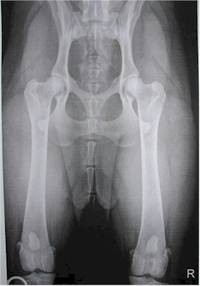

Hier ein Hund mit gesunder Hüfte.

Gesundheitsprobleme und Erbkrankheiten:

Jeder Züchter

muß seine Hunde einer HD und ED Röntgen unterziehen.

Nur HD (Hüftgelenksdysplasie) und ED (Ellbogendysplasie) freie Hunde sind für eine weitere Verpaarung einer Zuchtlinie geeignet und es liegt auch in der Verantwortung der Verbände und Züchter darauf zu achten, nur jene Elterntierefür die Weiterzucht zuzulassen.